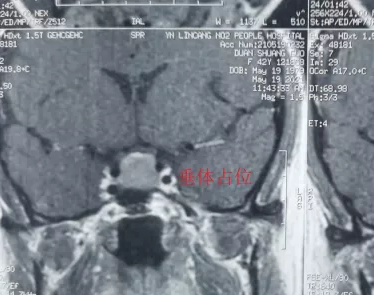

完善檢查后,段女士被確診為無功能性垂體腺瘤并卒中。通過積極術前準備,楊金雷主任帶領的外一科醫護團隊,在省級專家指導及我院麻醉手術室的精誠協作下,為段女士開展了顯微鏡下經鼻蝶垂體腺瘤切除術。手術歷時1.5小時后順利結束。